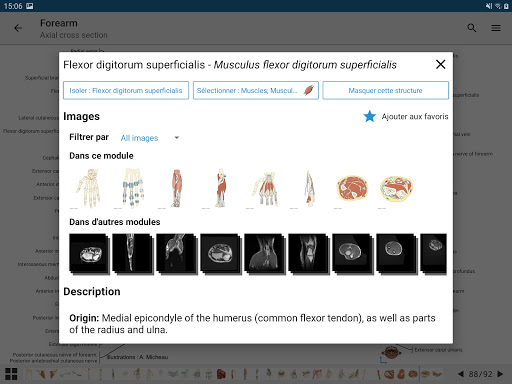

e-Anatomy memiliki lebih dari 26.000 gambar yang berisi serangkaian gambar dalam tampilan aksial, koronal, dan sagital serta radiografi, angiografi, gambar diseksi, bagan anatomi, dan ilustrasi. Semua gambar medis diberi label dengan cermat, lebih dari 967.000 label tersedia dalam 12 bahasa termasuk Terminologia Anatomica Latin.

- Ketuk label untuk menampilkan struktur anatomi

*Peningkatan tampilan detail bagian anatomi untuk memudahkan identifikasi dalam gambar modul saat ini dan modul lainnya.

-Dalam tampilan detail struktur anatomi , pin sekarang menunjukkan struktur terkait di semua gambar yang ada

- "Filter oleh", dalam tampilan detail Anda sekarang dapat menyaring gambar yang mengandung struktur anatomi oleh modalitas